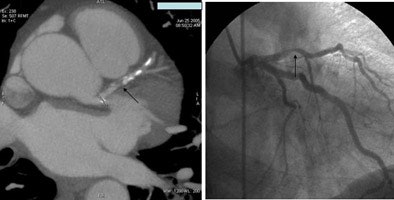

![]() |

| A 59-year-old man presented with classic chest pain symptoms to the ER five days earlier. He was asymptomatic upon presentation to the practice, but opted for an office-based CTA rather than wait three weeks to see a cardiologist. Images top to bottom: Right coronary artery stenosis (arrows) shown on 64-slice CTA at left, cardiac catheterization at right. Next, a normal left circumflex artery (arrows) is depicted on 64-slice CTA at left, cardiac catheterization at right. Next two image sets: Left anterior descending artery stenosis (arrows) is seen on 64-slice CTA at left, cardiac catheterization at right. Bottom image shows excellent outcome on cardiac cath following stenting. |